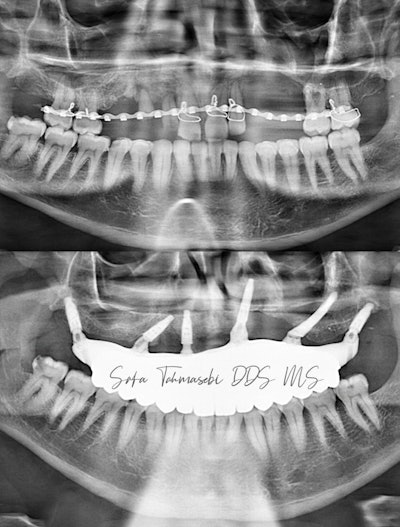

Figure 5: Before and after panoramic x-ray of John Doe's teeth.